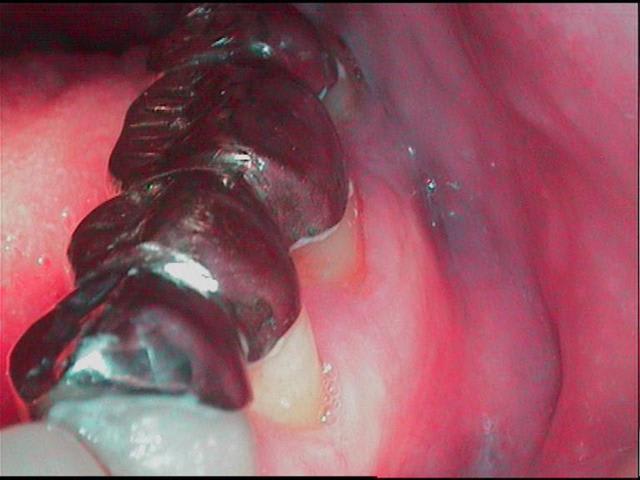

Rettt canaux qxszs4 - Eugenol